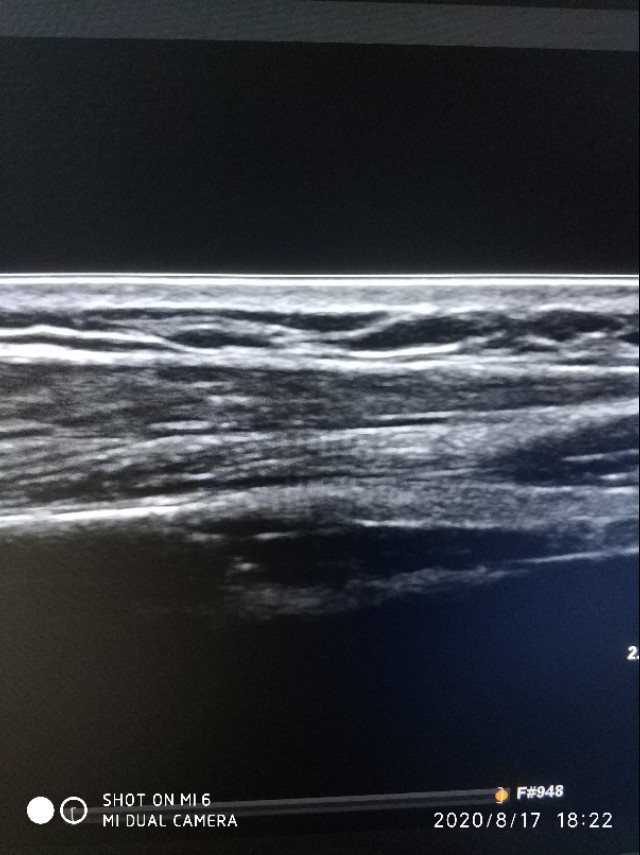

现在皮肤上囊性包块,表皮样囊肿居多,那么什么是表皮样囊肿呢,它形成的原因可能是由于皮肤外伤或手术,将皮肤上皮组织植入皮下所引起,不过呢,要问病人病史,病人一般是否认包块处有外伤史。还有一种说法是它可能是皮肤单胚层源性的真性良性肿瘤,在没有外伤手术等证据的情况下,后者可能显得更有说服力。表皮样囊肿囊内一般充满表皮角化物或白色颗粒状油脂样物。多发生于手脚部,颈背部,臀部及阴囊。呈圆形或椭圆形,囊壁光滑(未感染或破裂时),生长缓慢,大小不一。在超声上表现为,在位置上位于皮肤的真皮层和皮下脂肪层间。

上图表皮层忽略不计,真皮层为回声增强的一层,再下方是黑白相间的脂肪层,再往下是肌肉层了。

第二点事边界十分清晰,如果囊肿破裂,周围会有积液。第三点是内容物是软化不同的角瓜上皮,超声上表现为细密的腺样强回声有时伴有细密的裂隙样低回声。第四没有血流信号。